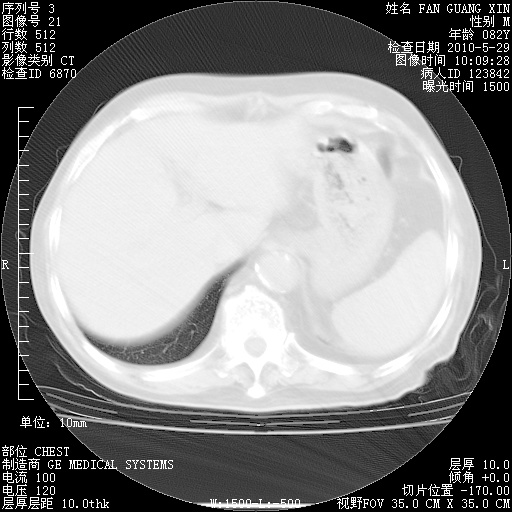

治疗3周后的肺部CT纵隔窗

再治疗10天后的肺部CT

再治疗10天后的肺部CT 纵膈窗

阅读此次胸部CT,肺间质渗出性改变较入院时有吸收。目前从体温、白细胞、中性分叶明显增高,肯定存在细菌感染(发生医院感染哦,若无消化道及泌尿系统等感染的依据,肺部感染可能大)。若你院头孢哌酮舒巴坦钠耐药率较高,同意你的方案,若48小时体温仍高,可考虑使用碳青霉稀类抗菌药物,同时可予超声雾化、注意滴数时加大液体量。白蛋白33.30g/L较低哦,需加强营养等支持治疗。